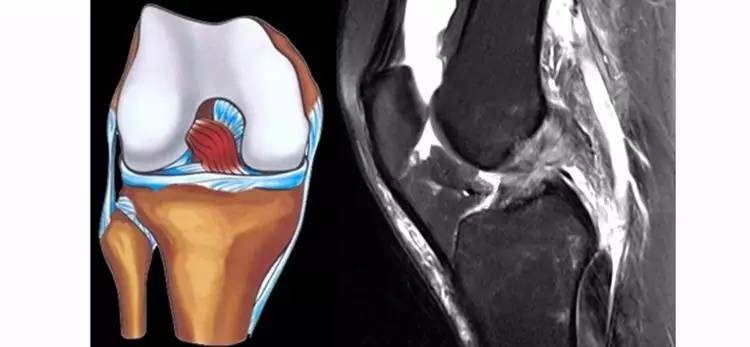

ACL损伤的MRI分级——

Grade1:韧带内损伤,无长度改变。

Grade2:韧带内损伤并长度延长。

Grade3:完全性韧带撕裂。

Grade1、2级为韧带的部分损伤,Grade3级为韧带的完全断裂。